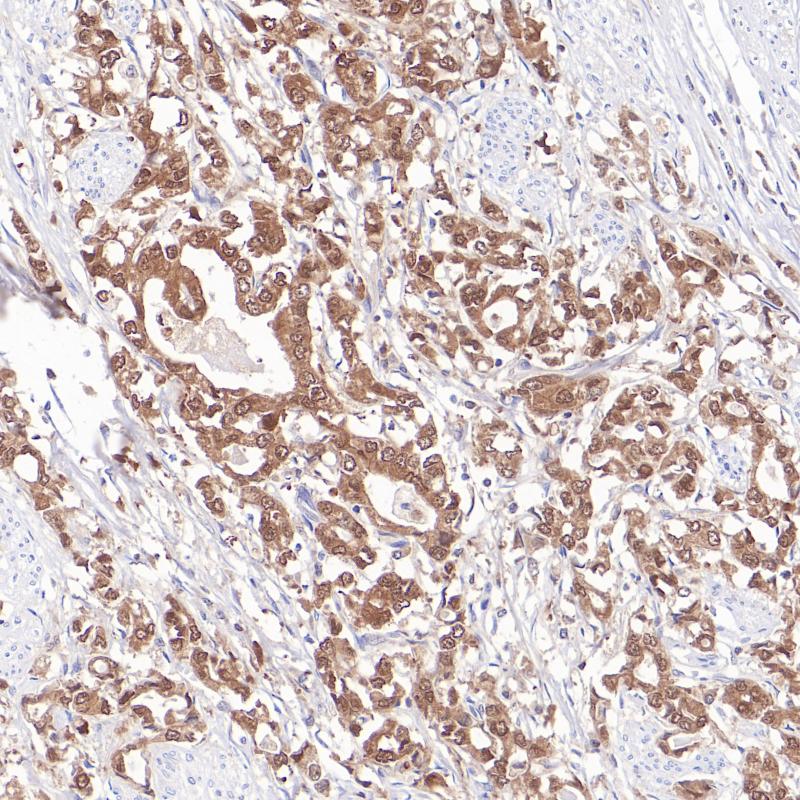

S100 重组兔单克隆抗体

阳性对照

阑尾

亚细胞定位

细胞质/细胞核